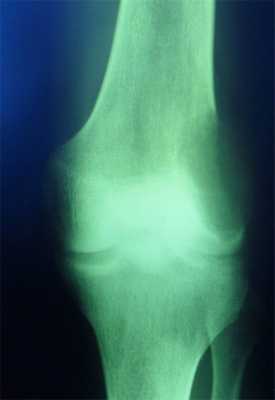

Доброкачественные образования костей

Опухоли костей - относительно редко встречающаяся патология. Доброкачественные образования чаще встречаются у лиц молодого возраста, как правило локализуются в трубчатых костях, при этом поражение нижних конечностей обнаруживается в два раза чаще чем верхних.

Диагностика опухолевых образований костей затруднена из-за отсутствия явных ранних симптомов - болевой синдром не выражен или отсутствует; рост опухоли отсутствует или очень медленный, деформация кости без изменения окружающих мягких тканей.

Возможности различных лучевых методов диагностики заболеваний скелета в настоящее время значительно расширились. Однако на первом этапе всем пациентам необходимо проводить классическую рентгенографию в стандартных проекциях, в зависимости от области интереса, поскольку этот метод является базовым и самым доступным, и позволяет практически во всех случаях получить необходимую информацию, поставить правильный диагноз, не используя дорогостоящие и малодоступные методики визуализации, такие как КТ и МРТ.

Для доброкачественных опухолей костей характерны такие общие рентгенологические признаки: четкие контуры, ободок склероза, часто вздутие кости, отсутствие периостальной реакции, медленный рост, солитарный характер поражения.